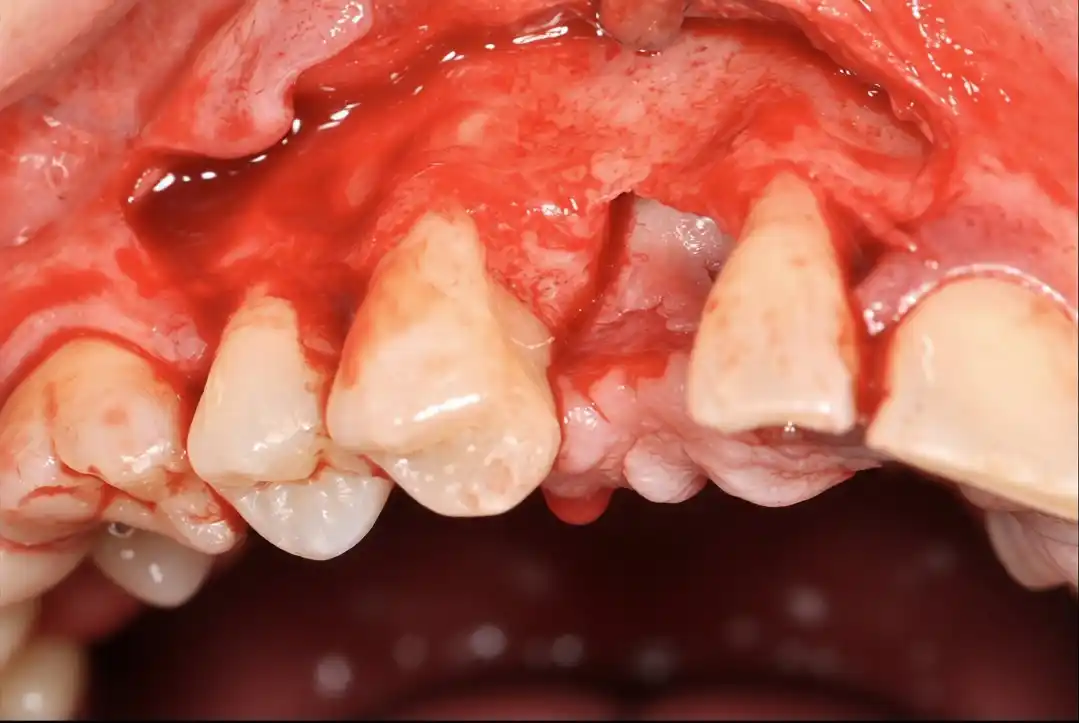

Managing complications: step by step clinical procedures

Full-thickness-flap